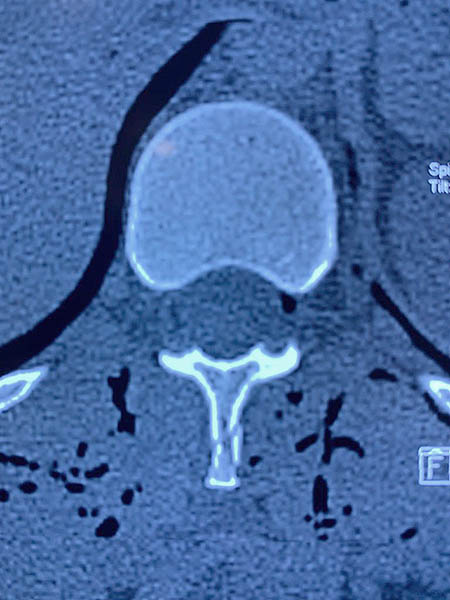

Imagenología del dignóstico

Dañada la vértebra T12

Vista lateral de la lesión